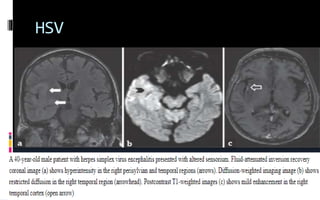

HSV

Imaging  CT subtle lowdensity within the anterior and medial parts of the temporal lobe and the island of Reil (insular cortex)  MRI

 Temporal lobeinvolvement is strongly suggestive of herpes simplex virus (HSV) encephalitis, although other herpes viruses (eg,VZV, Epstein-Barr virus, human herpesvirus 6)  areas of increased signal intensity in the frontotemporal, cingulate, or insular regions of the brain on T2 ,(FLAIR), or dwi MRI common in HSV encephalitis.  thalamus or basal ganglia may be observed in the setting of encephalitis due to respiratory viral infection, Creutzfeld-Jacob disease, arbovirus, and tuberculosis